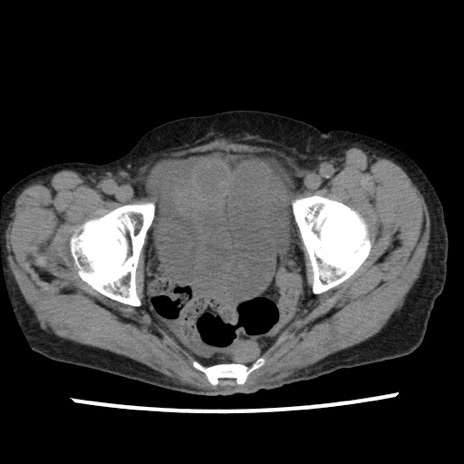

矢状断像

【症例】80歳代女性

【主訴】腹痛

【現病歴】8時間前から腹痛あり来院。

【既往歴】糖尿病、脂質異常症、子宮体癌にて子宮全摘術

【身体所見】意識清明・会話良好だが腹痛で苦悶様、全腹部にわたって反跳痛と圧痛あり

【データ】WBC 13600、CRP 0.14、LDH 224、CK 90